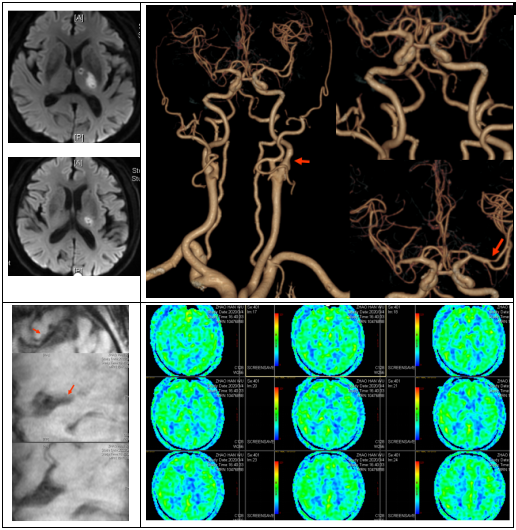

绿色通道初步评估后,卒中单元进一步评估患者血管条件,脑灌注影像及病灶血管壁的高分辨核磁共振